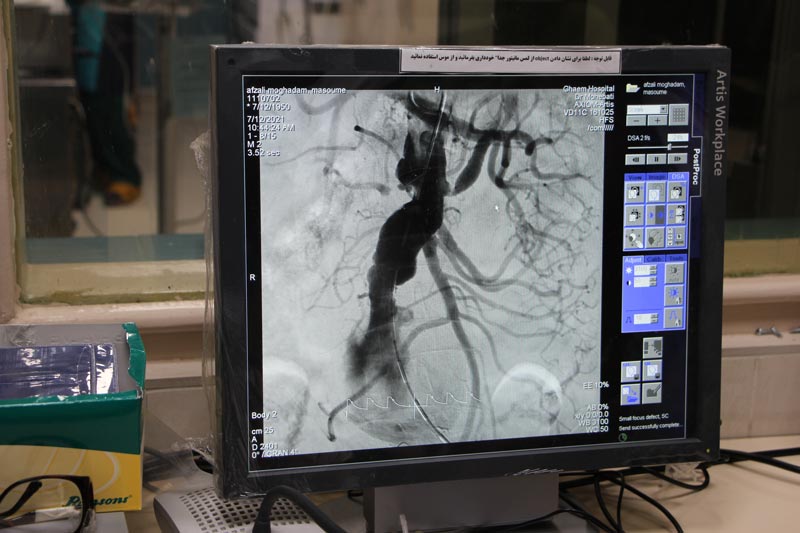

عمل ترمیم آنوریسم شکمی به روش بسته (EVAR ) با تلاش متخصصین برای نخستین بار در بیمارستان قائم (عج) انجام شد

مدیر مرکز آموزشی ، پژوهشی و درمانی قائم (عج )در گفتگو با وب دا گفت: با تلاش و کمک تیم اینترونشن بیمارستان که تیمی متشکل از متخصصین قلب و عروق بسیار باتجربه است، برای نخستین بار این عمل پیچیده روی بیمار 73 ساله دیابتی که سابقه عمل قلب باز داشت و ریسک مجدد عمل قلب باز بسیار زیاد بود با موفقیت به صورت بسته (داخلی عروقی) انجام شد.

دکتر خداپرست با اشاره به اینکه علاوه بر تهران در چند بیمارستان مشهد پزشکان ،از روش بسته(EVAR) برای درمان بیماران استفاده می کردند خاطر نشان کرد: آنوریسم آئورت شکمی یکی از بیماریهایی بود که غیر از عمل جراحی باز راه دیگری برای درمان نداشت و جز عملهای سخت و سنگین محسوب می شد و عوارض بسیاری برای بیماران در پی داشت .

وی اظهار کرد: خوشبختانه در سالهای اخیر پیشرفتهای قابل توجهی در درمان بیماران قلبی صورت گرفته ، پزشکان موفق شدند بدون عمل قلب باز ، با ایجاد شکافهای کوچک در ناحیه کشاله ران ، به روش بسته(داخلی عروقی) با کمترین عوارض به درمان بیماران قلبی بپردازند.